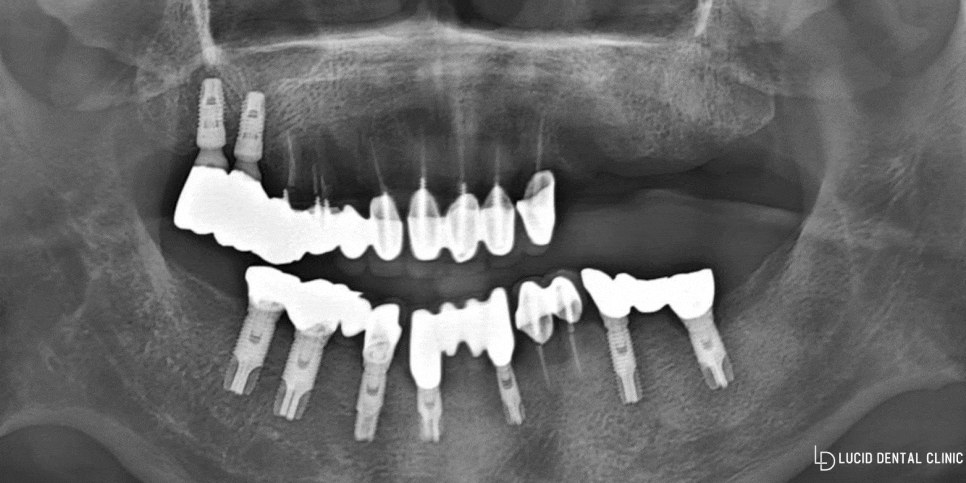

논현동 치과 첫 내원 당시

엑스레이 촬영을 통하여

구강 내 상태를 정확히 진단했습니다.

왼쪽 어금니를 모두 상실한 것을

확인할 수 있었으며,

임플란트 수술 받는데는

큰 지장이 없었습니다.

게다가 따로 신체 질환도 없었으며

뼈 또한 소실없이 어느 정도

갖추고 있었기 때문에

큰 무리없이 진행할 수 있다는

진단을 내렸습니다.

그런데 구강 내를 살펴보니

임플란트를 꽤 여러 군데 심었으며,

다른 치아들은 이미 신경치료를

모두 받은 것을 확인할 수 있었습니다.

원래 구강 건강이 그리 좋지 않았던 터라

병원을 좀 자주 들렸다고 말씀하셨습니다.